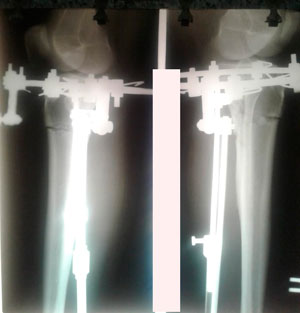

рентген в 90 дней.